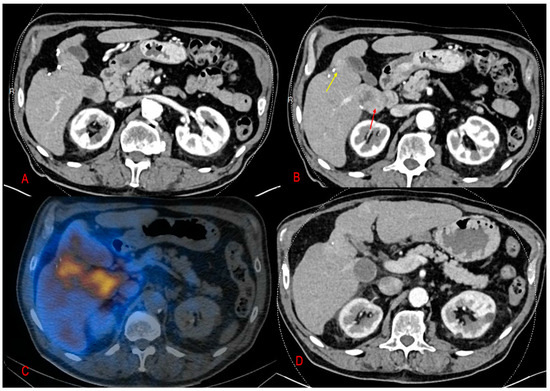

2. Results

3. Discussion

4. Methods and Materials